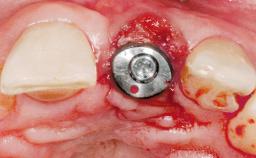

Immediate Placement of an Implant in a Maxillary Left Central Incisor Site

A 33-year-old female patient presented with an upper left central incisor that required extraction after a failed endodontic therapy. The tooth had been traumatized when the patient was a teenager and had undergone several endodontic treatments, including two apicectomy procedures. The patient was in good health and did not smoke. Clinical examination showed that the patient had a high lip line. In full smile, the gingival margins of the upper teeth were visible to the first molars. The gingival margins of central incisors 11 and 21 were only just showing. Examination of tooth 21 confirmed that the tooth was mobile and had hypererupted by 1 mm.

| Placement Protocol | Immediate implant placement |

| Tooth Site | Maxillary incisor or canine |

| Socket Morphology | Single-root socket |

| Socket Integrity | Damage to one or more bone walls |

| Bone Volume | Damage to one or more socket walls |